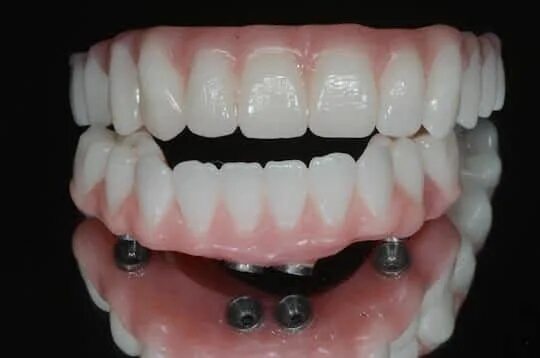

Ол он 4